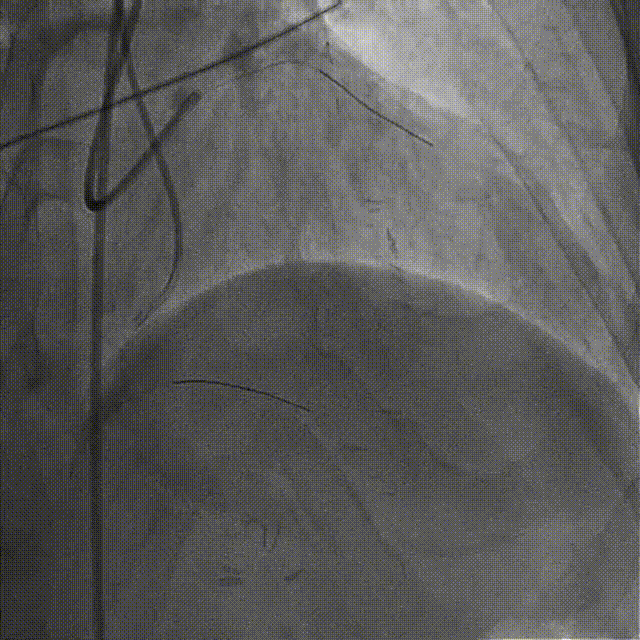

置7F UBS 3.75、6F JR 4.0指引导管至左右冠开口,分别送入Marvel导丝至LCX远段、RCA远端加强支撑,行双侧造影。

在微导管支撑下,Sion导丝无法经OM1心外膜侧枝逆向至LAD远段,改送Fielder XT-R导丝逆向至LAD远段。

HighTrack微导管跟进至闭塞病变远端,正向工作导丝做指引,应用Fielder XT-A导丝逆向通过闭塞段至LM内,反复尝试调整导丝未能进入正向指引导管。